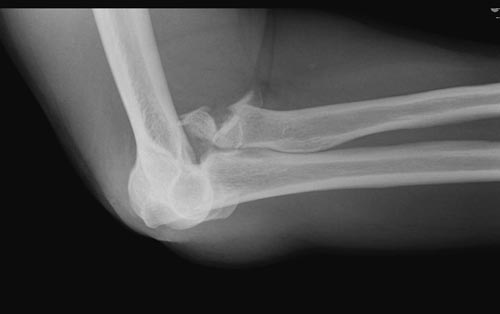

Re: ПЕРЕЛОМ ГОЛОВКИ ЛУЧЕВОЙ КОСТИ.